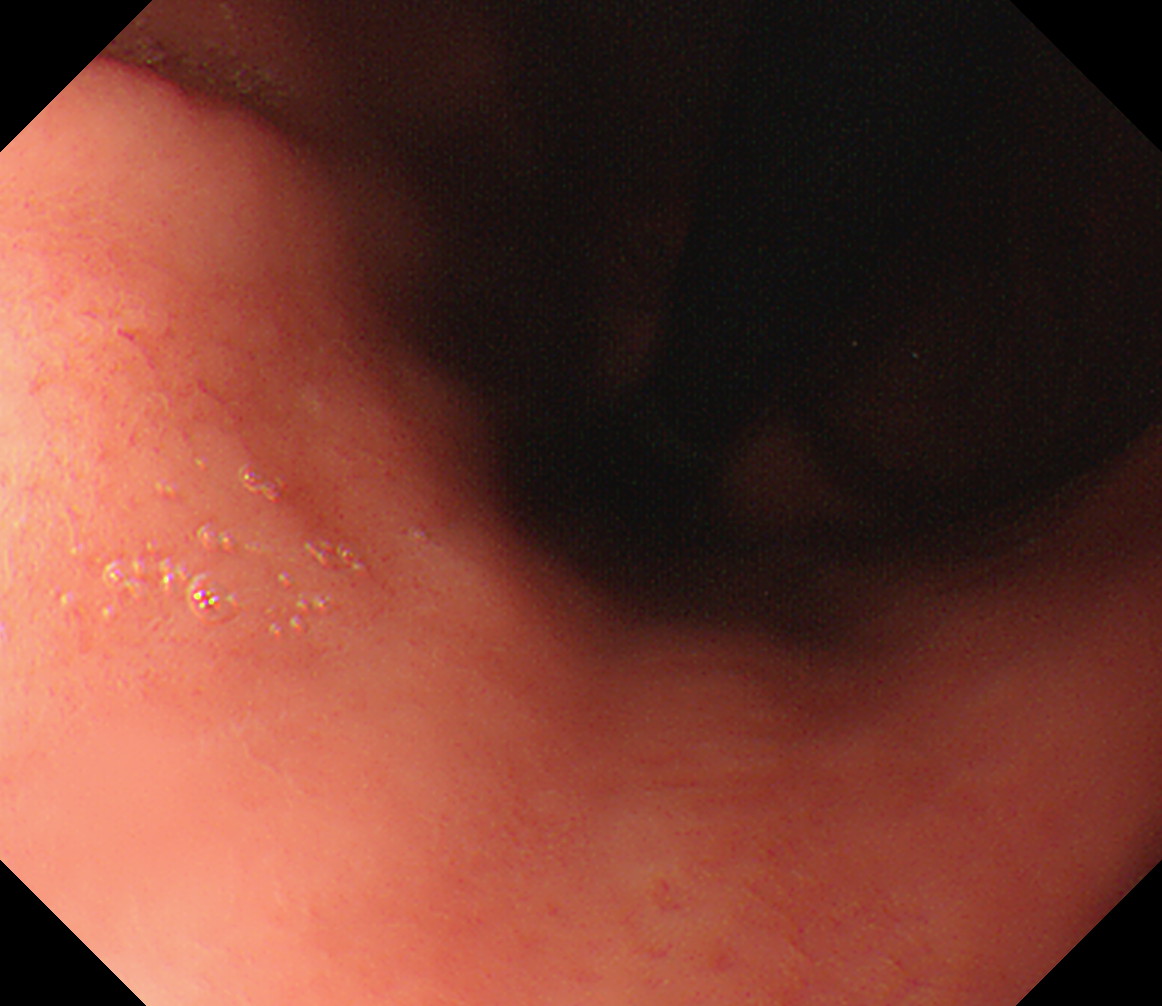

1 食道中部 門歯から約25cm 中部食道

2 食道下部 門歯から約35cm 食道下部